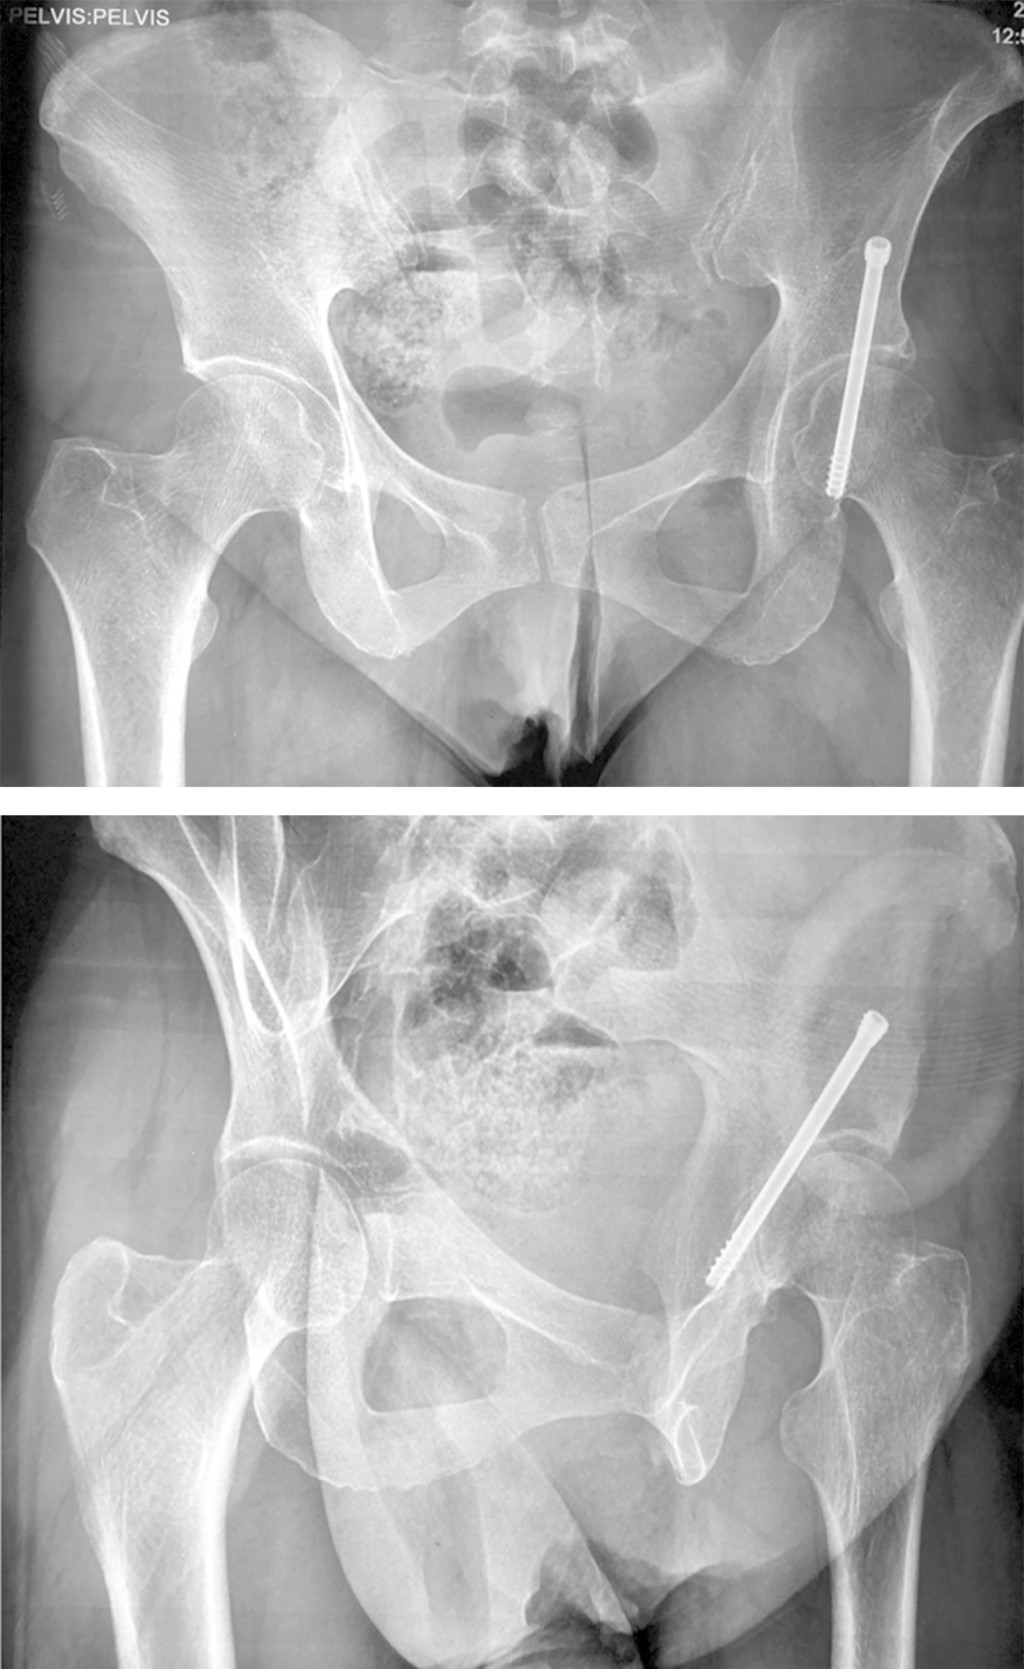

También se puede asociar con fracturas acetabulares. Ocurre debido al bloqueo del suministro de sangre a la cabeza femoral (bola) por daño arterial que conduce a la necrosis de la cabeza del fémur. Prevención. Puede prevenir las fracturas acetabulares al: Usar cinturones de seguridad y conducir con seguridad.. An updated bibliographic review on the classification of acetabulum fractures was made. There were analysed important aspects of the international classification that divides these fractures into partially articular, with affection of one or both columns, and complex articular that specify all the variants in every case.